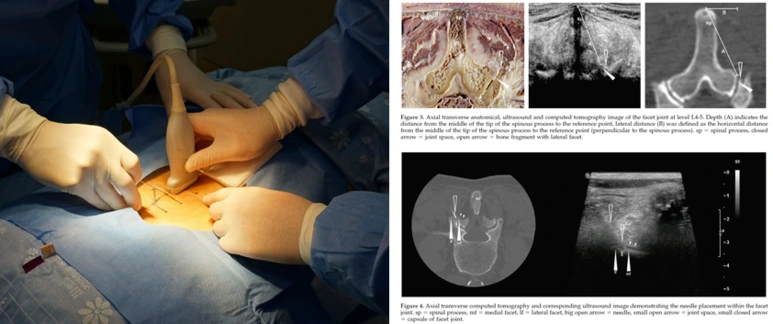

허리디스크 치료 왜 신경근이완술이 필요한가요?

- 디스크가 탈출되어 신경을 압박하면 신경유착이 발생하게 되는데, 이 부위를 직접 도침을 자입하여 박리하여야 합니다. 신경의 재유착을 방지하고, 신경의 염증을 제거하며, 통증을 줄이기 위한 신경근약침을 활용하면 통증을 줄일 수 있습니다.

image.png?type=w773

- 실제 청연한방병원 의료진이 참여한 연구에서 1년 이상의 추적 관찰 결과, 퇴행성 척추질환 (추간판 탈출증, 퇴행성 디스크, 척추관협착증) 환자에게서 30% 이상의 통증 감소가 확인되었습니다